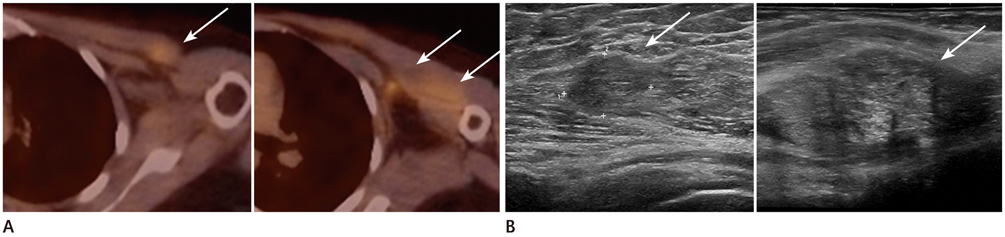

Our database revealed 922 breast cancer patients who underwent surgery from January 2008 to July 2011. We included 20 patients with negative findings on routine follow-up but with new hypermetabolic lesions on FDG-PET/CT. All underwent second-look examination [breast ultrasound (US) = 14, chest CT scan = 6]. A total of 17 cases were pathologically verified and 3 were diagnosed with follow-up imaging.

The locations were in the axillae (n = 7), breast (n = 6), chest wall (n = 3), cervical/supraclavicular (n = 3), and internal mammary (n = 1). Of the 20 hypermetabolic lesions, 10 were pathologically confirmed malignancies. Of the 14 patients who had undergone US, 7 had suspicious findings and 5 were confirmed as malignancies. Of a total of 6 patients who had undergone CT scans, 5 had suspicious findings and all turned out to be malignancies. The positive predictive value of the second-look examination was 83.3% (10/12).

Second-look examination and pathologic confirmation should be performed for newly appearing hypermetabolic lesions on FDG-PET/CT in order to exclude loco-regional recurrence in breast cancer patients.